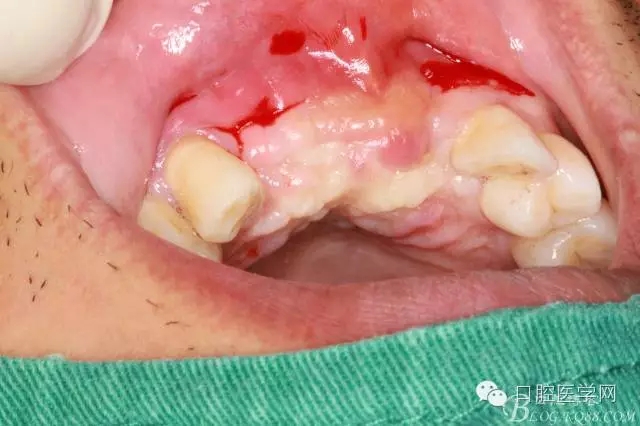

遺憾沒有保留術(shù)前口內(nèi)照片,只有術(shù)后的。

植入種植體左側(cè)3510,右側(cè)4010,植骨Bioss,蓋膜Cytoplast。骨膜減張垂直褥式縫合加間斷縫合。

后期的修復(fù)工作由之前的轉(zhuǎn)診醫(yī)生后續(xù)處理,由于GBR過程骨膜減張導(dǎo)致角化牙齦不足3mm,建議角化牙齦移植改變其更好的牙齦生物型。